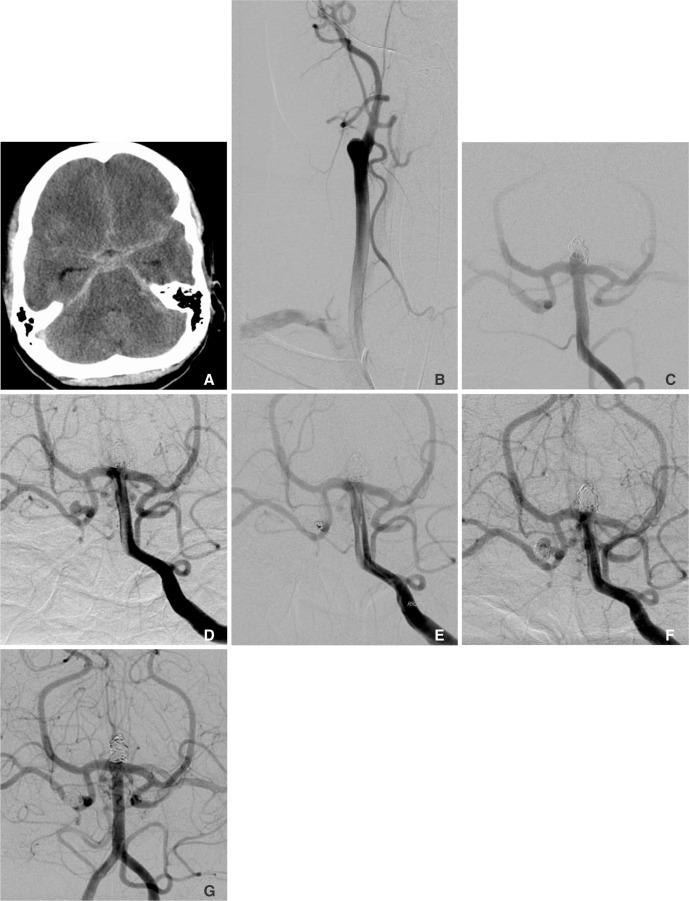

This case series and literature review serves to illustrate a relationship between spontaneous carotid occlusion and rapid enlargement of cerebral aneurysms.

In our case series, we demonstrated that increased hemodynamic stress on collateral vessels caused by a spontaneous carotid occlusion may contribute to unusually rapid aneurysm growth and/or rupture.

在我们的病例系列中,我们证明了自发性颈动脉闭塞引起的侧支血管血流动力学压力增加可能导致动脉瘤异常快速生长和/或破裂。